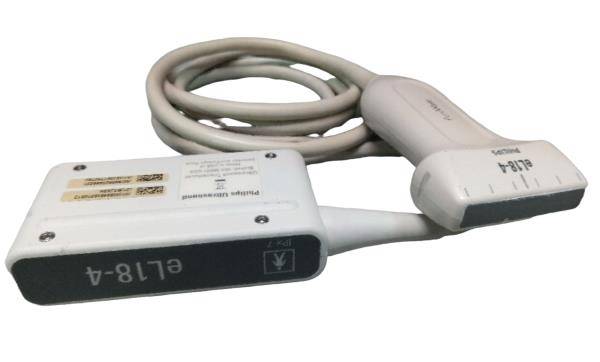

Globalmed Clearprobe USB 7.5 MHz Handheld Vascular Ultrasound Probe

Sale price$ 1,843.36

Regular price$ 2,248.00

GlobalMed ClearProbe Vascular USB 7.5 MHz VA Handheld Ultrasound Probe W/Case

Sale price$ 239.21

Regular price$ 291.72

Good Agilent Optigo Portable Cardiac M2430A Ultrasound System & 21420A Probe!

Sale price$ 7,795.73

Regular price$ 9,506.99